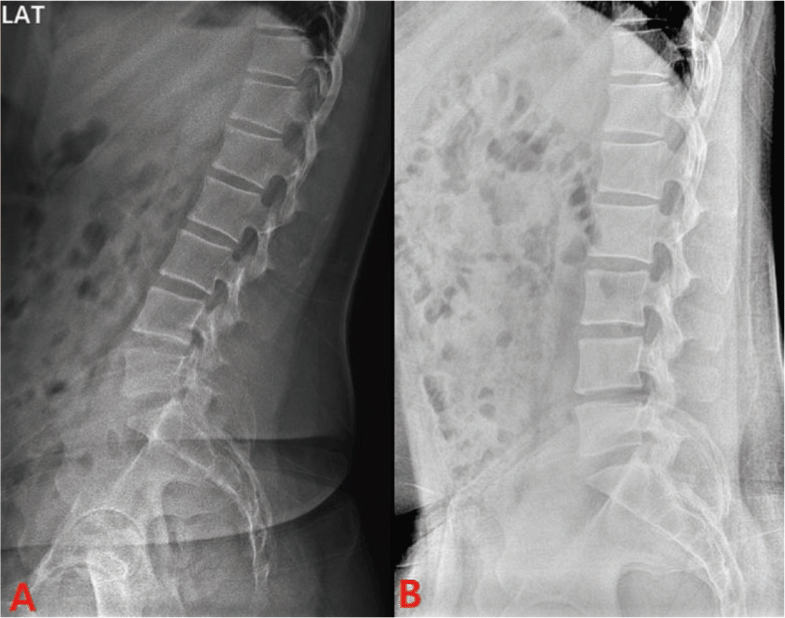

Radiographic measurements were taken using the Jumong General X-ray System (SG HealthCare, Seoul, Republic of Korea) and confirmed using the picture archiving and communication system (PACS) of ViewRex3 (ver 3.0.8.8(1.0), TechHeim Co., Ltd., Seoul, Republic of Korea). LL, SS, PI, and PT were measured before surgery, one month after surgery, and after 12 weeks of intervention (5 months after surgery) to confirm alignment.10,11 Neutral and extension segment lordosis angles (SLA) were measured before surgery, one month after surgery, and after 12 weeks of intervention to confirm the movement of each lumbar segment on radiographs of the patient's perceived neutral and extension positions, and the difference in movement between the extension and neutral positions was determined before surgery and after intervention. One month after surgery, only the neutral position was taken due to pain (Table 2) (Figure 1).12

In the case of SLA, an angle closer to zero means that the upper and lower segments are parallel, while a positive angle means that the space between the posterior segments is narrower, and a negative angle means that the space between the anterior segments is narrower.12

The SLA results in the neutral position of this study showed that the upper lumbar spine, such as T12-L1 and L1-2, showed an alignment change from a gradually decreased lordotic curve to a gradually increased lordotic curve, and the L3-4, L4-5, and L5-S1 segments showed a decrease in angle change after MSI intervention and gained intervertebral space. These results are consistent with a decrease in PT values in the neutral position. An increase in PT value indicates pelvic retroversion, which occurs with hip joint extension. However, in this study, the radiographic measurements were taken in a standing position, and these results suggest that the standing position measured before surgery and one month after surgery was actually a state of hip joint extension, and it can be considered that the MSI-based exercise program in this study is moving toward a neutral position rather than a hip-pelvis-hip complex with extension in a standing position. Previous studies have suggested that the normal PT value is less than 15°, and interventions focusing on motor control of the hip joint and lumbar spine are needed in future treatment to reduce the current PT value of 19.8°.10

The difference between the SLA values in the neutral position and in the supination state before and after the intervention showed that the extension movement was evened out in all segments after the intervention compared to before the surgery. In particular, the excessive L4-5 segmental movement in the extension state due to the L4-5 disc rupture, which was suspected to be the main problem of the preoperative back pain, seems to have been reduced by the rehabilitation, which is consistent with the results of increased muscle strength of the muscles dominated by the pain and the segment. Exercises that emphasize segmental movements of the spine improve spinal mobility and reduce overall peri-vertebral muscle tension.15 Trunk flexion and extension using a foam roller, which was the intervention in this study, is designed to recognize the position of the spinal segments and the combined movements of the lumbar-pelvic-hip joint complex through trunk flexion and extension on a foam roller, and it is likely that segmental movements were learned through the application of these exercises.